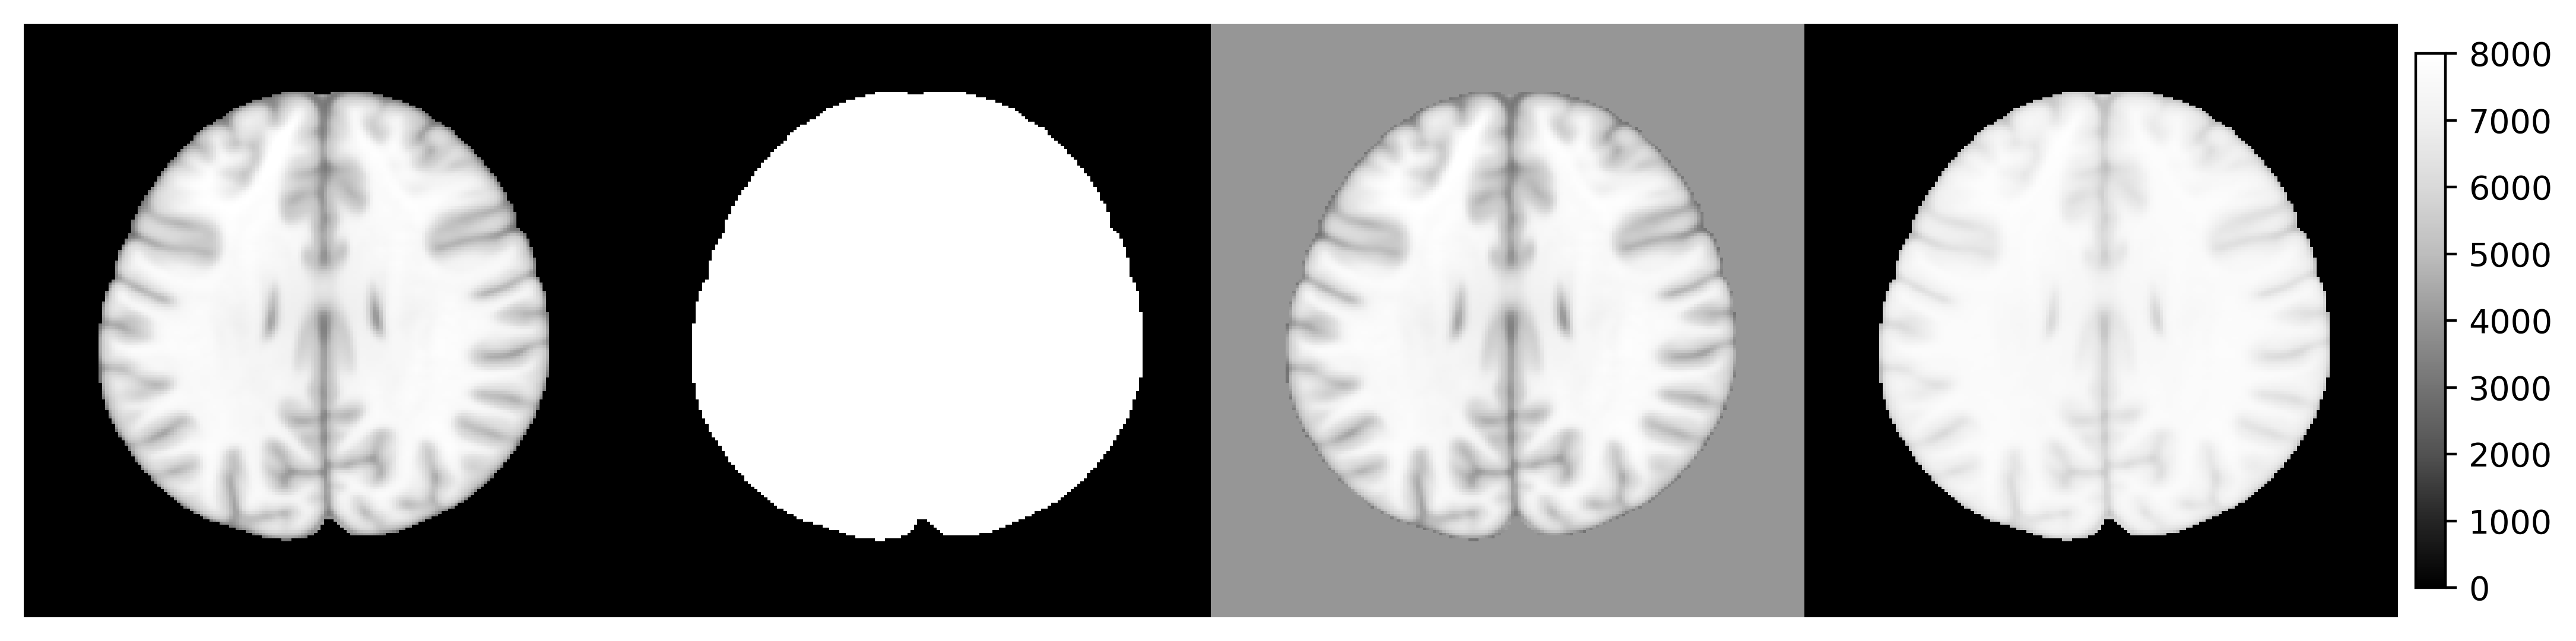

library(rpyANTs)

image <- ants$image_read(ants$get_ants_data('mni'))

print(image)

dim(image)

range(image)

y1 <- (image > 10) * 8000

y2 <- image

y2[y2 < 10] <- 4000

y3 <- log(image + 1000)

y3 <- (y3 - min(y3)) / (max(y3) - min(y3)) * 8000

ants_plot_grid(

list(image, y1, y2, y3),

slices = 100, shape = c(1, 4),

vmin = 0, vmax = 8000

)